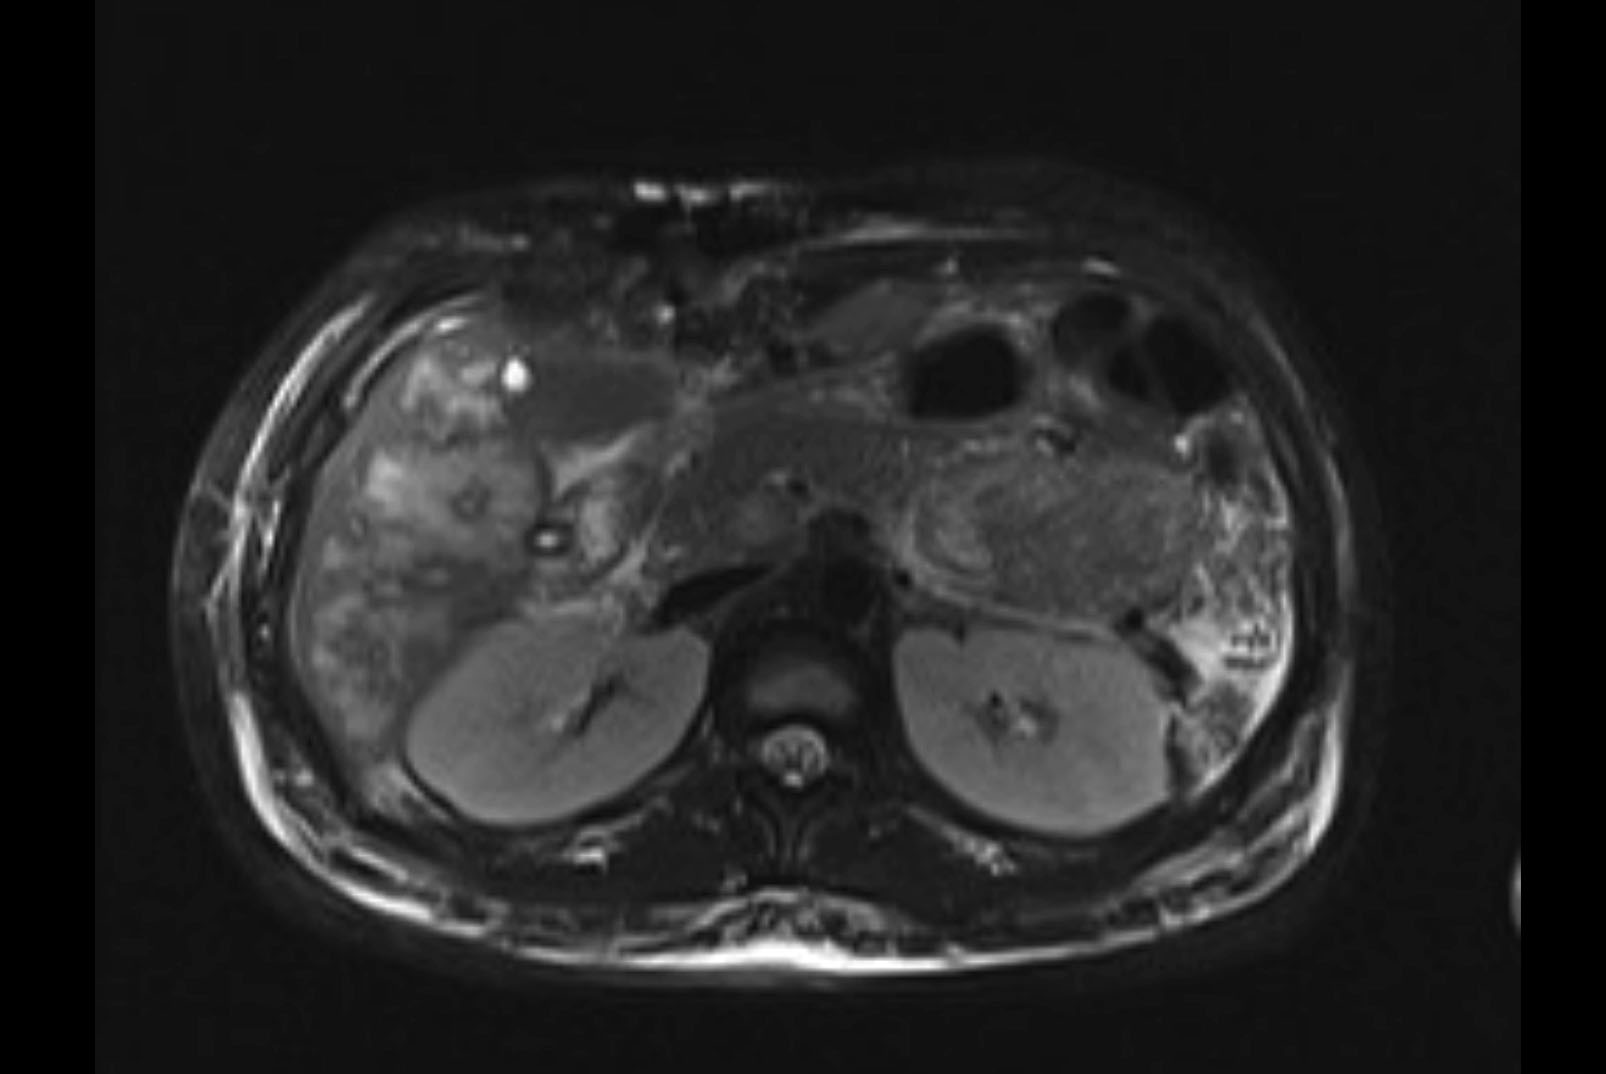

Imaging Analysis

Look through the patient's CT scan to identify any areas of concern for the necessary procedure.

MRI T1

MRI T2

Based on initial findings, which issue(s) would you be most concerned about?